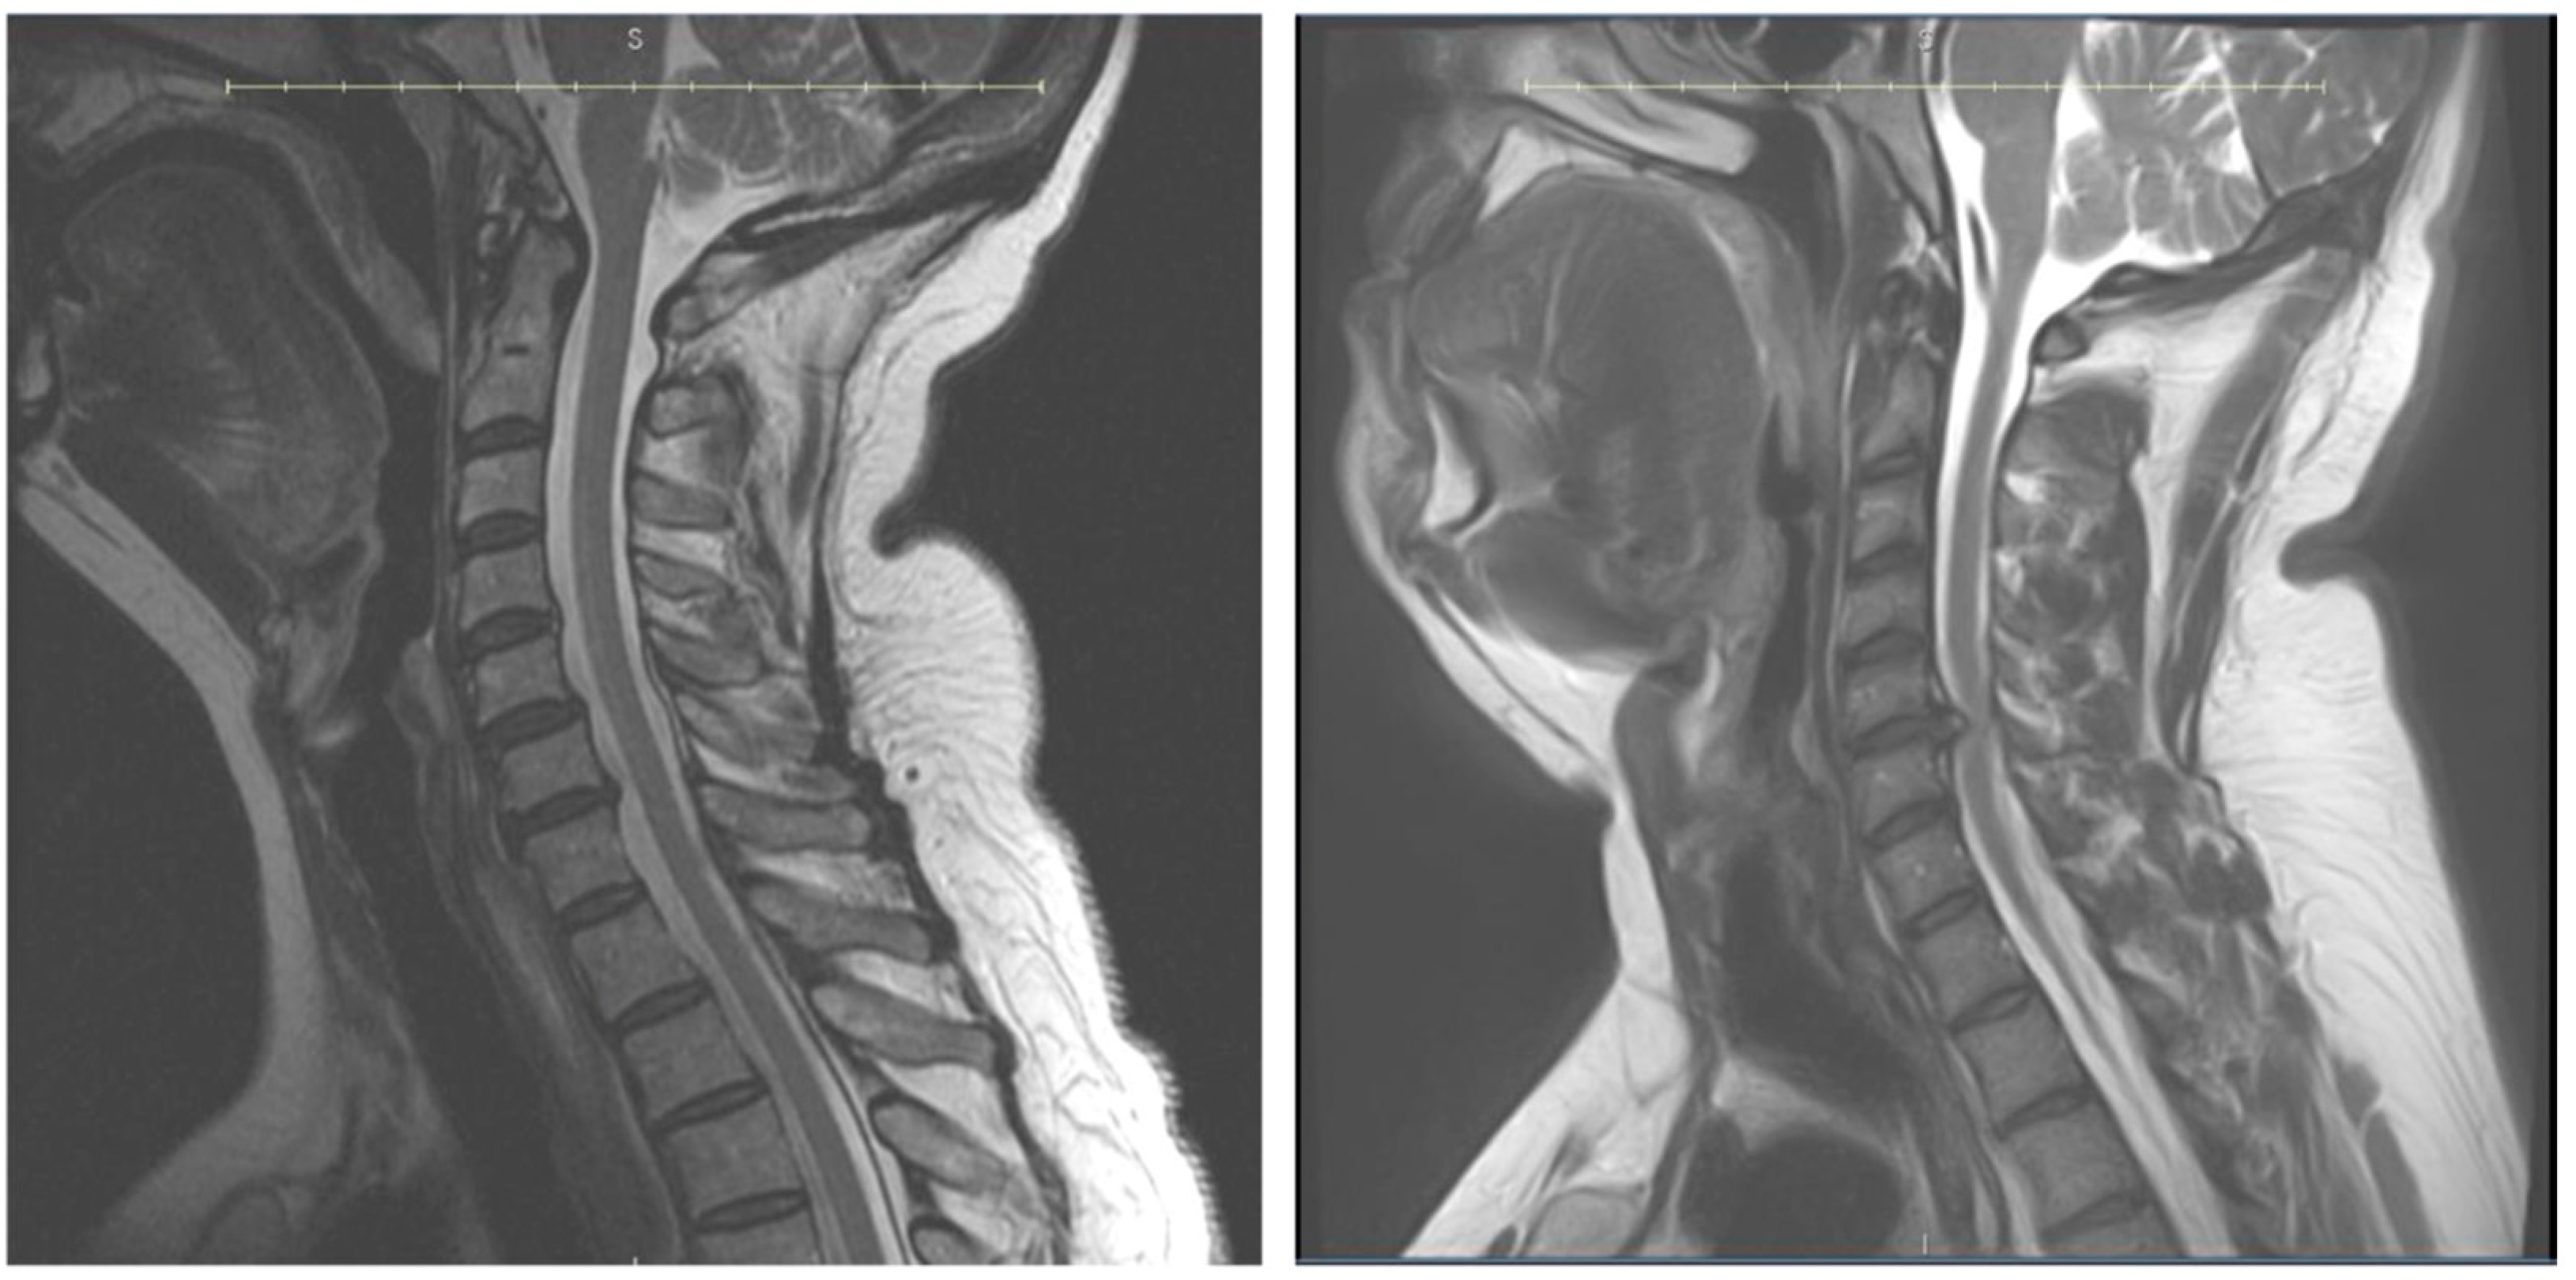

- He, B.; Sheldrick, K.; Das, A.; Diwan, A. Clinical and Research MRI Techniques for Assessing Spinal Cord Integrity in Degenerative Cervical Myelopathy—A Scoping Review. Biomedicines 2022, 10, 2621. [Google Scholar] [CrossRef] [PubMed]

- Martin, A.R.; Tetreault, L.; Nouri, A.; Curt, A.; Freund, P.; Rahimi-Movaghar, V.; Wilson, J.R.; Fehlings, M.G.; Kwon, B.K.; Harrop, J.S.; et al. Imaging and Electrophysiology for Degenerative Cervical Myelopathy [AO Spine RECODE-DCM Research Priority Number 9]. Glob. Spine J. 2022, 12, 130S–146S. [Google Scholar] [CrossRef]